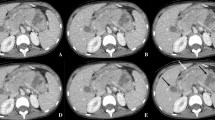

The quantitative analysis of vessel lengths showed that Veo™ images depicted PA, SA and RA vessels of longer lengths than on ASIR™ images (Table 4 and Fig. 2). Furthermore, the number of branch vessels depicted in the apical segment of the right upper lobe PA was consistently greater in number for each subject (Fig. 3) and significantly different on Veo™ (mean number of branch vessels ± standard deviation = 8.7 ± 2.5) vs. ASIR™ (4.3 ± 1.7, P < 0.0003). This better depiction of branch vessels by Veo™ was also well visualized on volume-rendered images (Fig. 4). Vessel tracking also illustrated how Veo™ provided an improved depiction in the terminal vessels with less noise and less variation in luminal size (Fig. 5).

A 5-year-old girl after liver transplantation and imaging obtained for evaluation of post-transplant lymphoproliferative disorder. Coned-down axial 10-mm maximum intensity projection images of the right hilum depict a greater number of pulmonary vessels and the vessels are visualized farther out into the periphery in the lung when images are created with Veo™ (a) than with ASIR™ (b). Both images are displayed with identical window width = 400 Hounsfield units and window level = 40 Hounsfield units